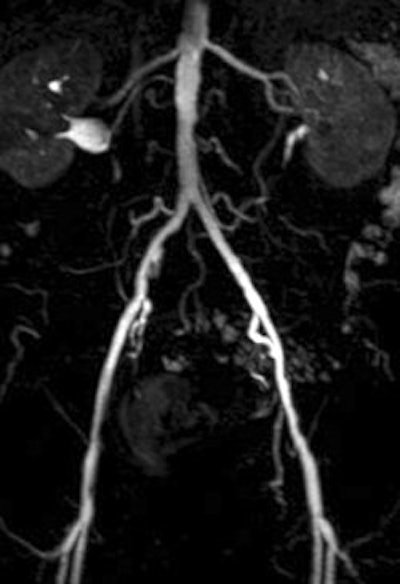

| A 78-year-old man with peripheral arterial occlusive disease. Lumbar arteries are evident with both MRI acquisition techniques. Iliac axis has good runoff on both sides after percutaneous transluminal angioplasty (above). Anteroposterior maximum intensity projection 3D fast low-angle shot (FLASH) intra-arterial MR aortogram obtained with standard technique (below). |